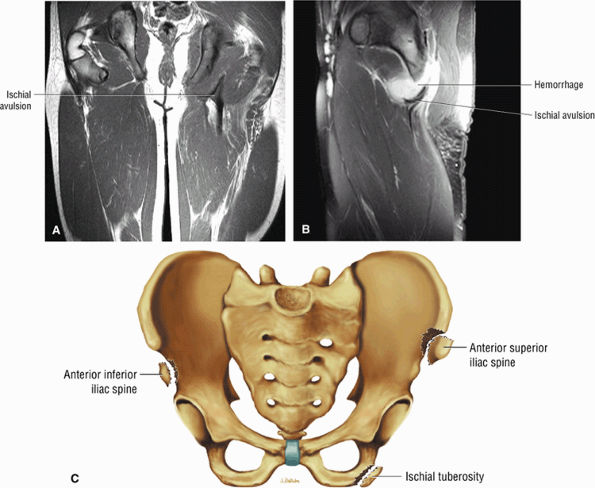

FIGURE 3.26 ● SEMIMEMBRANOSUS The semimembranosus extends the thigh and flexes the leg. It is part of the hamstring muscle group (biceps femoris, semimembranosus, and semitendinosus) in the posterior thigh. Except for the short head of the biceps, the origins of the hamstring tendons are from the ischial tuberosity and are involved in ischial avulsion fractures in the young athlete.